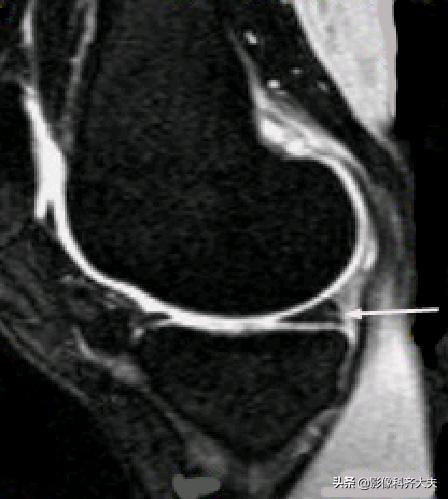

Ⅱ级:表现为水平的、线形的半月板内高信号,可延伸至半月板的关节囊缘,但未达到半月板的关节面缘。病理:粘液变性范围较Ⅰ级大,显微镜下软骨基质的的多细胞区内可见裂隙和胶原碎片